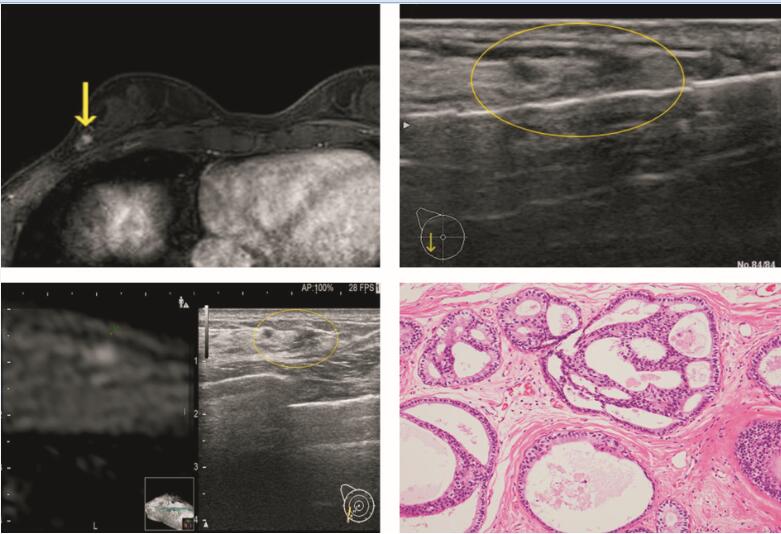

剪切波弹性成像与彩色多普勒联合诊断乳腺纤维上皮肿瘤的临床实践

冯瑞卿, 傅仲带, 曹磊, 欧妍妍, 黄健东

2020, 20(06):  694-698.  DOI: 10.3969/j.issn.1009-976X.2020.06.02

摘要 ( )   PDF (2003KB) ( )

参考文献 | 相关文章 | 计量指标

目的 探讨剪切波弹性成像(SWE)联合彩色多普勒在诊断乳腺纤维上皮肿瘤中的价值。方法 选择2017年8月至2019年5月在我院因乳腺肿块进行超声诊断并接受组织学活检与手术切除的患者。根据纳入标准分纤维腺瘤组和叶状肿瘤组,共59例患者入组,纤维腺瘤组43例,叶状肿瘤组16例。所有患者均获得B超、SWE和彩色多普勒超声检查;平均弹性(E平均)、最大弹性(E最大)和血管信号由SWE和多普勒超声测定。结果 两组的临床与超声特征包括:叶状肿瘤组病变的平均体积大于纤维腺瘤组(P<0.05),叶状肿瘤组的不均匀回声比纤维腺瘤组更多(P<0.05)。叶状肿瘤组BI-RADS分类高于纤维腺瘤组(P<0.05),叶状肿瘤的组织E平均和E最大显著高于纤维腺瘤组(P<0.05),叶状肿瘤组有较高的血流信号(与纤维腺瘤组比较,P<0.05)。另一方面,彩超和SWE的平E平均值的特异性和准确性高于B超检查,E最大的特异度高于B超检查,敏感性略低于B超检查。E平均>40.4 kPa或高血流信号或E最大>48.2 kPa或高血流信号为标准的SWE和彩超联合应用可将诊断的敏感性和PPV提高到100%。结论 与乳腺叶状肿瘤相比,纤维腺瘤有较低的僵硬度和较少的血管数量的倾向。联合应用SWE和多普勒超声中,平均弹性值和最大弹性值在鉴别可疑病例方面显示更高的诊断价值。